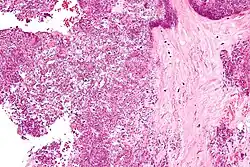

| Polarized light microscopy of CPPD, showing rhombus-shaped calcium pyrophosphate crystals with positive birefringence. | |

Arthrocentesis, or removing synovial fluid from the affected joint, is performed to test the synovial fluid for the calcium pyrophosphate crystals that are present in CPPD. When stained with H&E stain, calcium pyrophosphate crystals appears deeply blue ("basophilic").[10][11] However, CPP crystals are much better known for their rhomboid shape and weak positive birefringence on polarized light microscopy, and this method remains the most reliable method of identifying the crystals under the microscope.[12] However, even this method has poor sensitivity, specificity, and inter-operator agreement.[12]